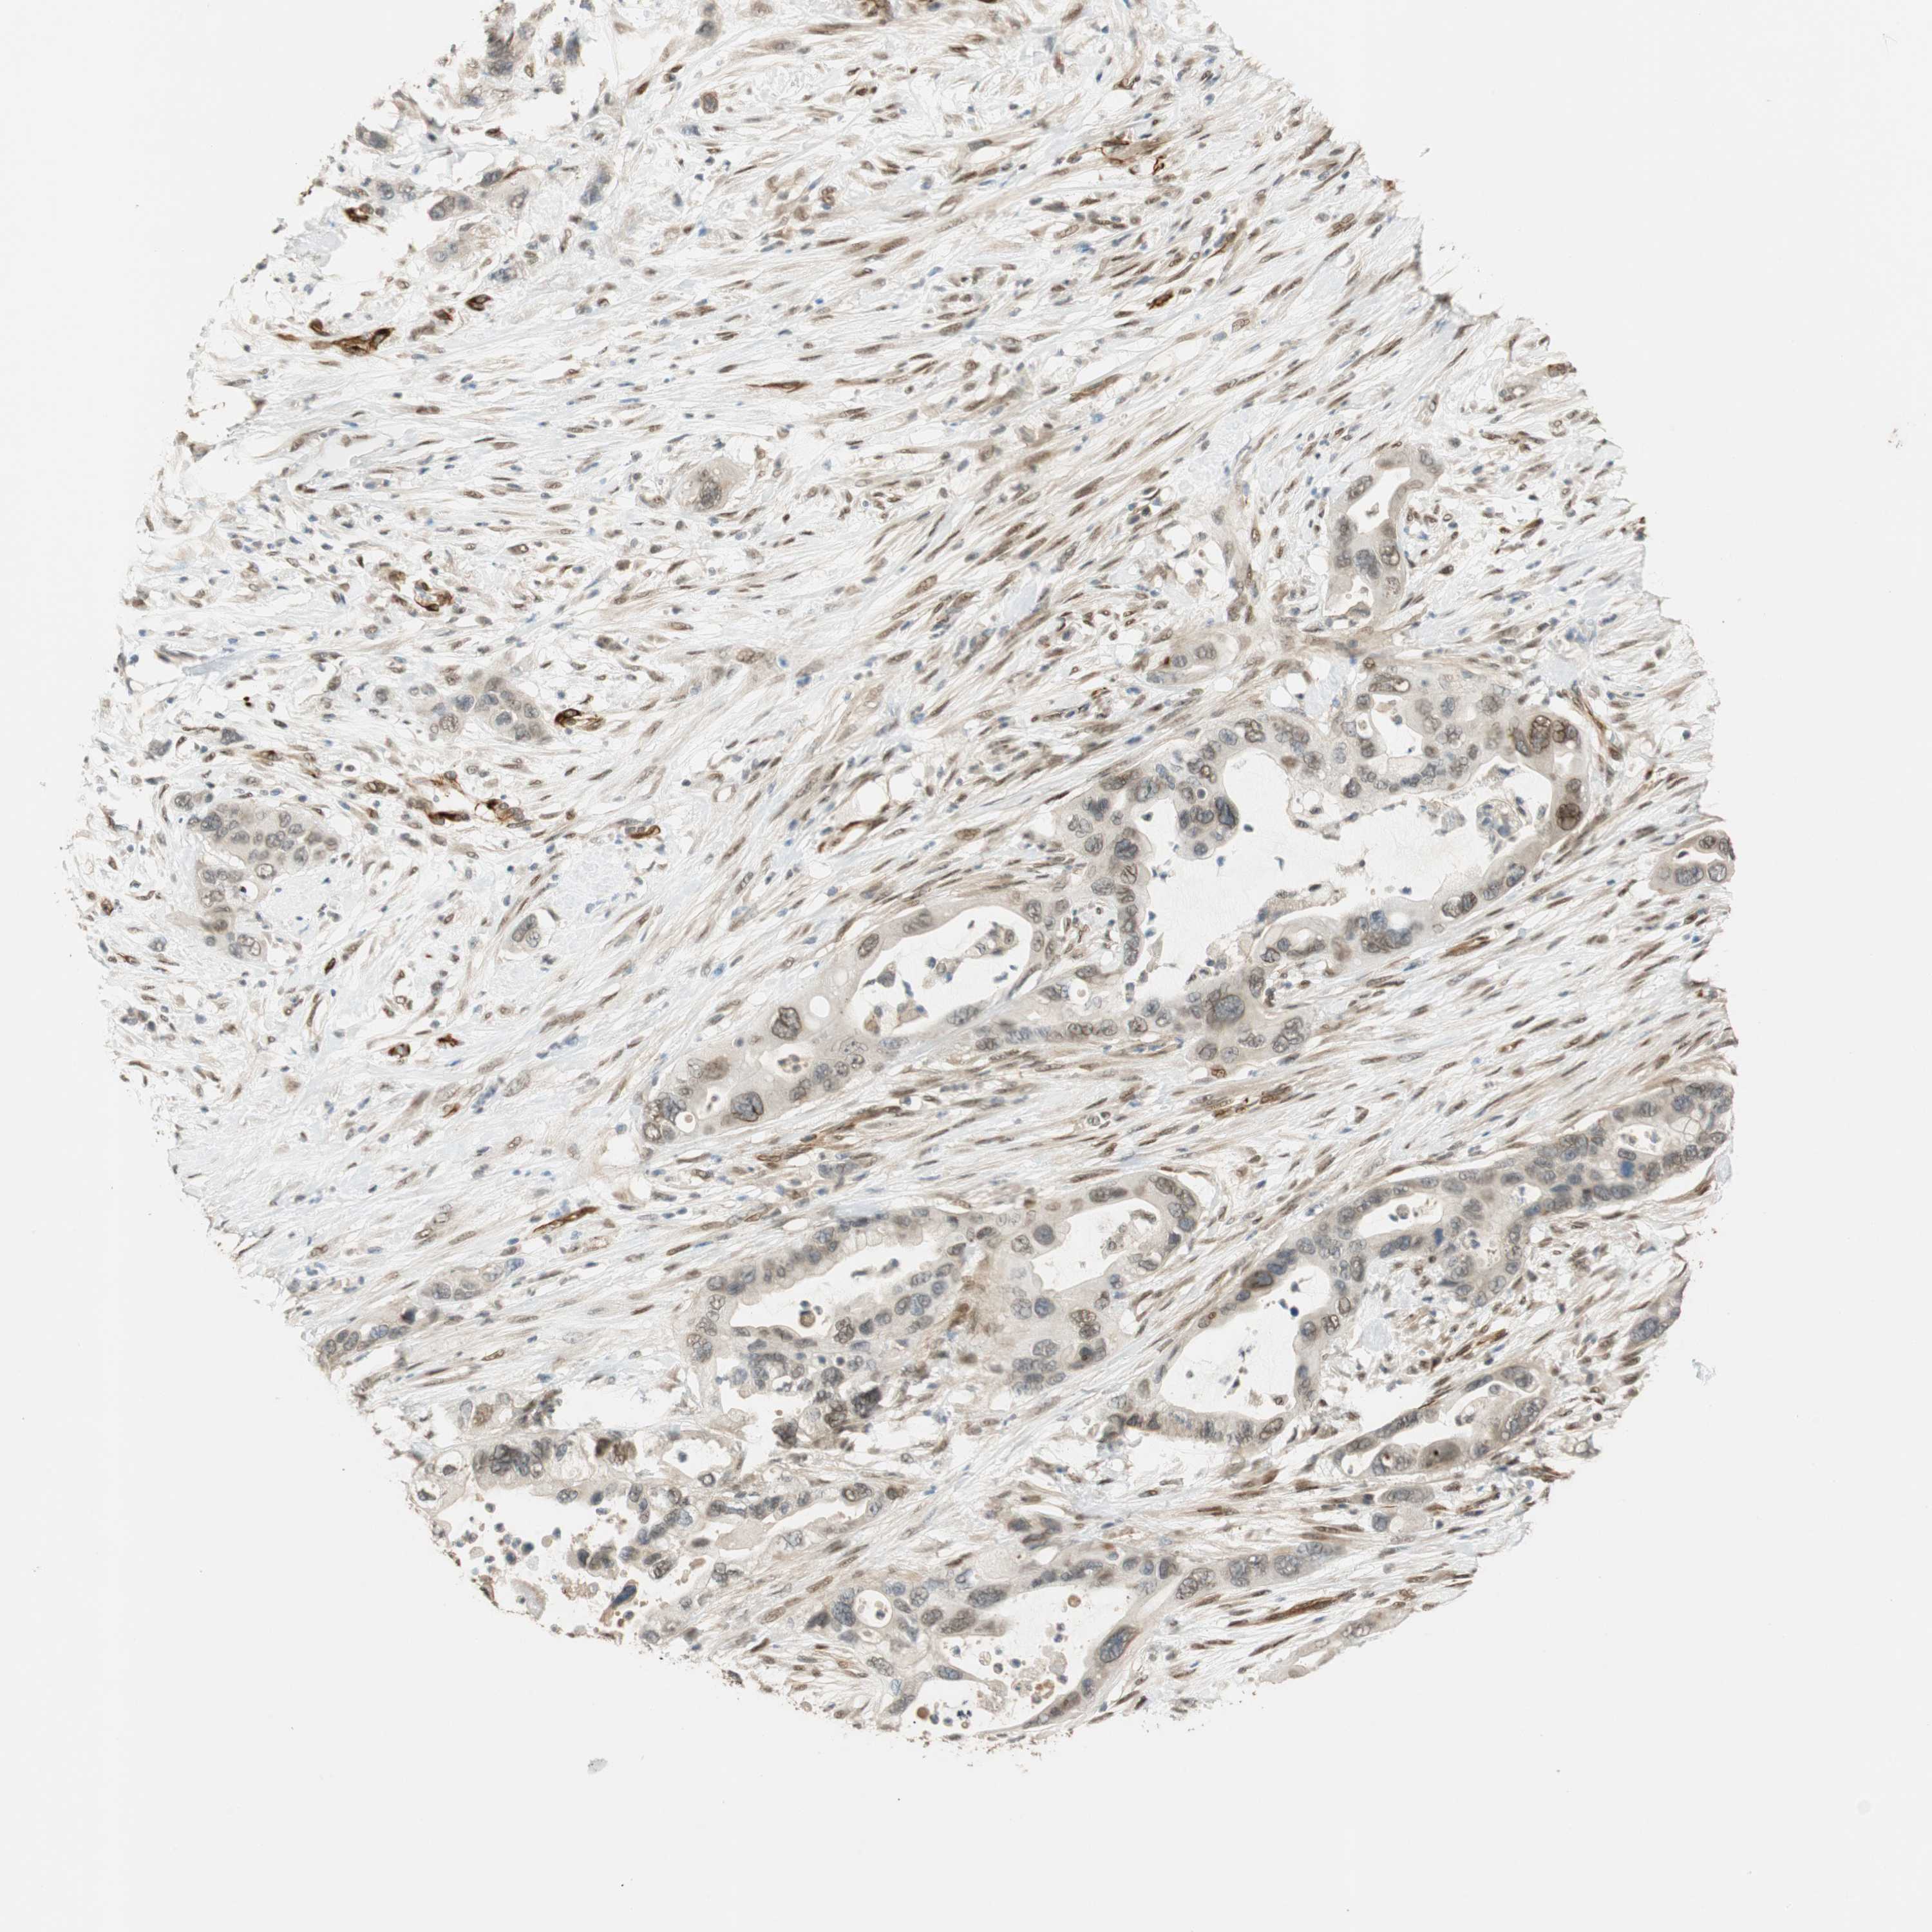

PANCREATIC CANCER - Protein expressioni

A mouse-over function shows sample information and annotation data. Click on an image to view it in a full screen mode. Samples can be filtered based on level of antibody staining by selecting one or several of the following categories: high, medium, low and not detected. The assay and annotation is described here.

Note that samples used for immunohistochemistry by the Human Protein Atlas do not correspond to samples in the TCGA dataset.

Antibody stainingi

Antibody staining in the annotated cell types in the current human tissue is reported as not detected, low, medium, or high, based on conventional immunohistochemistry profiling in selected tissues. This score is based on the combination of the staining intensity and fraction of stained cells.

Each image is clickable and will lead to virtual microscopy that enables deeper exploration of all samples and also displays staining intensity scores, fraction scores and subcellular localization as well as patient and tissue information for each sample.

Antibody HPA007007

Antibody HPA026111

Antibody CAB005889

Antibody CAB058692

Staining

High

Medium

Low

Not detected

Intensity

Strong

Moderate

Weak

Negative

Quantity

>75%

75%-25%

<25%

None

Location

Nuclear

Cytoplasmic/membranous

Cytoplasmic/membranous,nuclear

Adenocarcinoma, NOS

Adenocarcinoma, metastatic, NOS